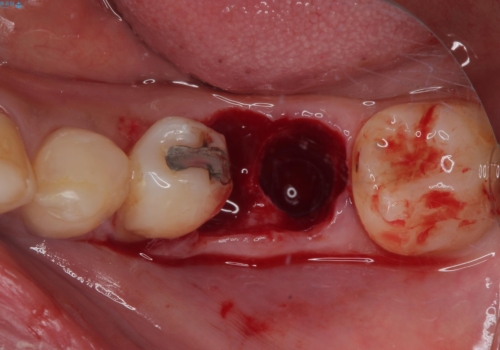

当院では、他院で抜歯と言われてきた歯を何とか保存する治療を多く行ってきましたが、レントゲン上で確認できるほど割れてしまっている歯はさすがに要抜歯と説明をし、インプラント治療を行うこととしました。

下顎大臼歯の抜歯即時埋入インプラント治療では、複数ある歯根のうち、後方の歯根部にインプラントを埋入することで一般的であり、今回破折して骨吸収が著しいのは前方の歯根であったため、事前に仮歯を用意した上で、抜歯即時埋入インプラントによる補綴治療を行うこととしました。